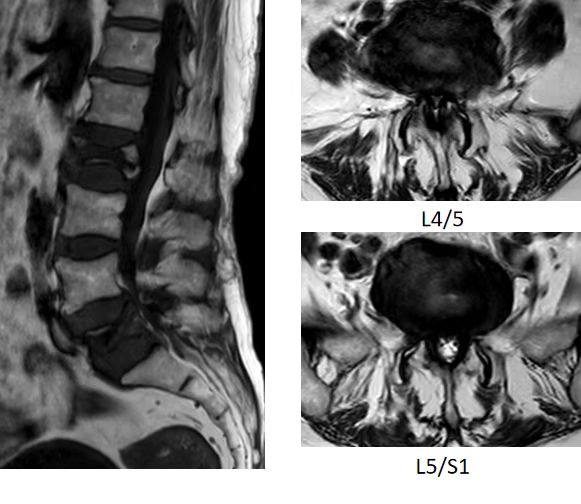

入院后,完善相关检查。经术前MRI显示:患者腰2椎体骨折、腰5椎体骨折、腰椎管重度狭窄。同时,患者还患有高血压、重度骨质疏松。经脊柱外科(骨四科)主任姜树东及科室团队研判,认为患者病灶多、症状重,结合患者高龄,团队评估后计划为患者进行腰2、5椎体成形术+单侧双通道脊柱内镜下椎管减压术(双节段双侧减压)。一次解决患者腰椎问题。

▲术前MRI显示腰2椎体骨折、腰5椎体骨折、腰椎管重度狭窄